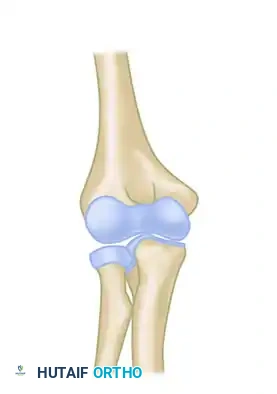

Pathoanatomy and Preoperative Considerations

Understanding the pathoanatomy of a chronic elbow dislocation is critical for successful surgical planning. Over time, the displaced joint undergoes profound structural changes:

- Triceps Contracture: The triceps brachii muscle shortens significantly, acting as a major tether preventing anatomical reduction.

- Capsuloligamentous Contracture: The medial collateral ligament (MCL) and lateral collateral ligament (LCL) complexes become fibrotic, shortened, and scarred to the displaced humeral condyles.

- Fibrous Pannus Formation: Dense fibrous tissue fills the olecranon and coronoid fossae, obliterating the normal articular spaces.

- Heterotopic Ossification: A "radial humeral horn" or other forms of periarticular ossification frequently develop due to chronic periosteal stripping and organized hematoma.